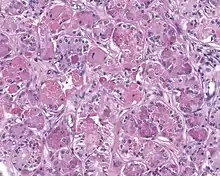

When reviewed by a pathologist, the findings are quite similar to fibrocystic changes of the breast, although they are different enough, that it is now recognized to actually represent a true neoplasm (clonal proliferation) through various studies.[5] Specifically, the lesions are usually well-circumscribed, containing lobules of haphazardly arranged ducts, myoepithelial cells, and acini that have abundant sclerosing or hyalinized fibrosis. Apocrine change is quite common in the ductal cells.[6] The ducts range from small ductules to cystically dilated spaces (more than 4 striated duct-widths across), often containing products of secretion or reactive histiocytes. A very curious and characteristic finding in all of the lesions is the presence of bright pink (eosinophilic) acinar granules (which are altered zymogen).